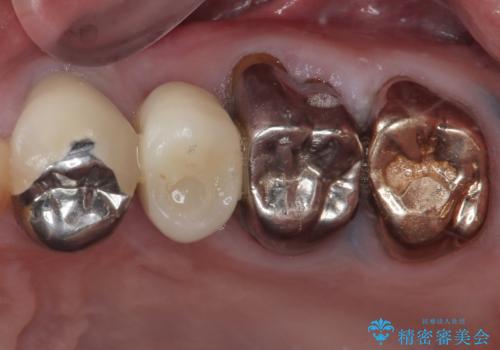

破折した奥歯 抜歯即時埋入インプラントによる補綴治療

- 舌側に膿の出口がずっと消えずに有り続けることを気にして来院された患者様です。

目視で歯根が破折していることが分かり、保存不可能と判断されたたため、抜歯即時埋入インプラントによる補綴治療を行うこととしました。